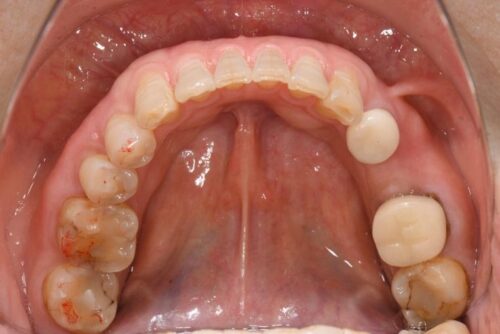

さて今回は、奥歯のインプラント治療の症例を紹介します。

【治療前】

【治療後】

| 治療内容 | 下顎奥歯のインプラント治療 |

| 治療期間 | 2ヶ月 |

| 治療費用 | 31万円( 税抜 ) |

| 副作用・リスク | 外科処置が伴うため、術後の疼痛・腫脹・出血・咬合痛などを生じる事があります。 麻酔を行う場合、腫れやむくみを生じる事があります。 また、被せ物や土台が外れたり、欠けたり、緩んだりする事があります。 |